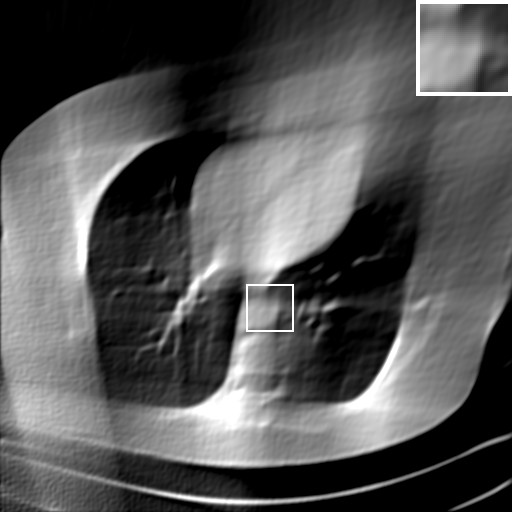

Fig. 4 presents the reconstruction results and residual images obtained by different methods for limited-angle reconstruction. As can be seen, the learning-based methods outperform the direct method and TV model, which exhibit serious artifacts in the missing angle region. Although the denoiser introduced by the FBP-Unet can somehow deal with the noises, the result still presents obvious artifacts. Compared to the SIPID, PD-net and FSR-nets, our LRIP-net1/2 can better preserve the image details and edges with less information left in the residual images. Thus, both the quantitative and qualitative results confirm that the low-to-high double-resolution strategy can improve the reconstruction accuracy for the limited-angle reconstruction problem.

We observe that the low-resolution image prior plays an important role in our method. More specifically, we compare the results of our LRIP-net with respect to different low-resolution priors, which are obtained by down-sampling rate of 1/2, 1/4, and 1/8, respectively. As can be seen in Table III, the best reconstruction results are obtained with the image prior reconstructed by the down-sampling rate of for 150∘, 120∘ and 90∘ limited-angle reconstruction. The visual comparison based on different image priors are also provided in Fig. 5, where obviously less artifacts are left in the reconstruction image by LRIP-net1/8. By comparing the running time, it is easy to see that the smaller the low-resolution image prior, the faster the LRIP-net works.